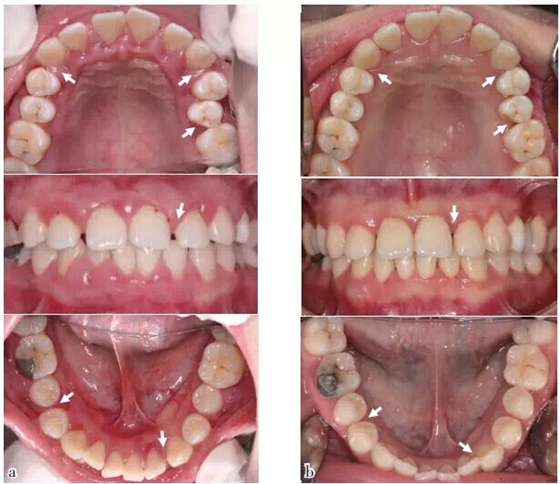

圖1 口內(nèi)照:與初診相比,SRP及咬合干預(yù)后,牙齦炎癥減輕,25排列整齊,多處牙間隙變小或關(guān)閉(箭頭),(a)2011/12初診,(b)2014/11評估